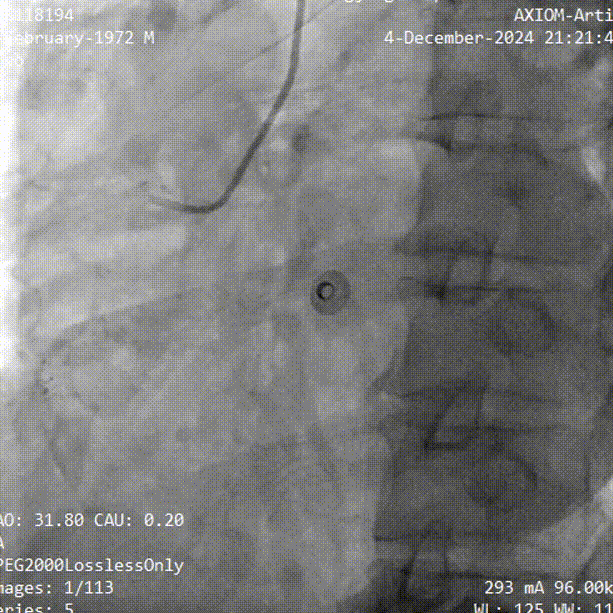

抽吸【例】量|【郑】论血栓抽吸操作